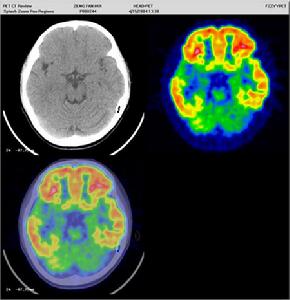

2.頭顱CT或MRI

平掃可見室管膜下腦室邊緣及大腦皮層表面多個結節狀稍低或等密度病灶,部分結節可顯示高密度鈣化,為雙側多發性,增強呈普遍增強,結節更清晰,可發現平掃不能顯示的結節。皮層和小腦的結節有確診意義。